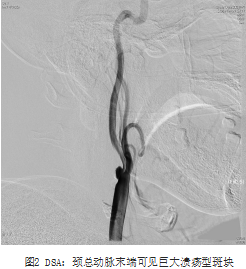

北京清华长庚医院4月28日电(通讯员 赵克强 吴巍巍)胡先生,62岁,3月前无明显诱因出现左手麻木、无力,5分钟后自行缓解,超声发现右颈动脉起始部狭窄70%,就诊于清华长庚医院血管外科。入院后完善术前检查,赵克强副主任医师为患者行全脑动脉造影提示:右侧颈动脉重度狭窄,颈总动脉巨大溃疡型斑块,延迟可见造影剂滞留于溃疡内;斑块超声造影及高分辨核磁分析,评估为不稳定斑块,极易脱落导致脑梗死。头颅MR可见脑内陈旧性多发腔隙性梗塞灶,以右侧前循环供血区域为著;患者原本计划行颈动脉支架微创手术,但考虑到支架无法完全覆盖巨大溃疡,围术期梗死风险较大,不适宜实施该项手术,经全科讨论后决定为患者进行颈动脉内膜剥脱术,血管外科吴巍巍主任、赵克强副主任医师在全麻下为老胡安全实施颈动脉内膜剥脱术,术后病理提示颈动脉巨大溃疡型斑块,斑块内出血;术后48小时顺利拔除伤口引流,1周拆线、康复出院,术后随访期间未再次出现TIA发作。